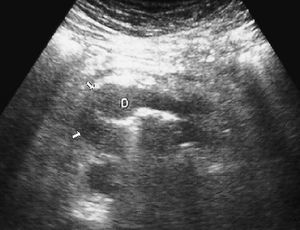

La enfermedad de Crohn afecta al duodeno de forma variable, apareciendo signos radiológicos en un 4% de los pacientes. Se manifiesta como un engrosamiento concéntrico y homogéneo de la pared, que puede producir estenosis de la luz intestinal (fig. 8). La existencia de actividad inflamatoria se identifica ecográficamente como aumento de la vascularización con modo doppler color. En la TC se observa la captación de la pared duodenal con afectación de la grasa adyacente.

Fig. 8--Enfermedad de Crohn duodenal. Corte ecográfico transversal donde se observa un engrosamiento concéntrico de la pared duodenal (D), que respeta la estructura de capas. VCI: Vena cava inferior; AO:aorta.